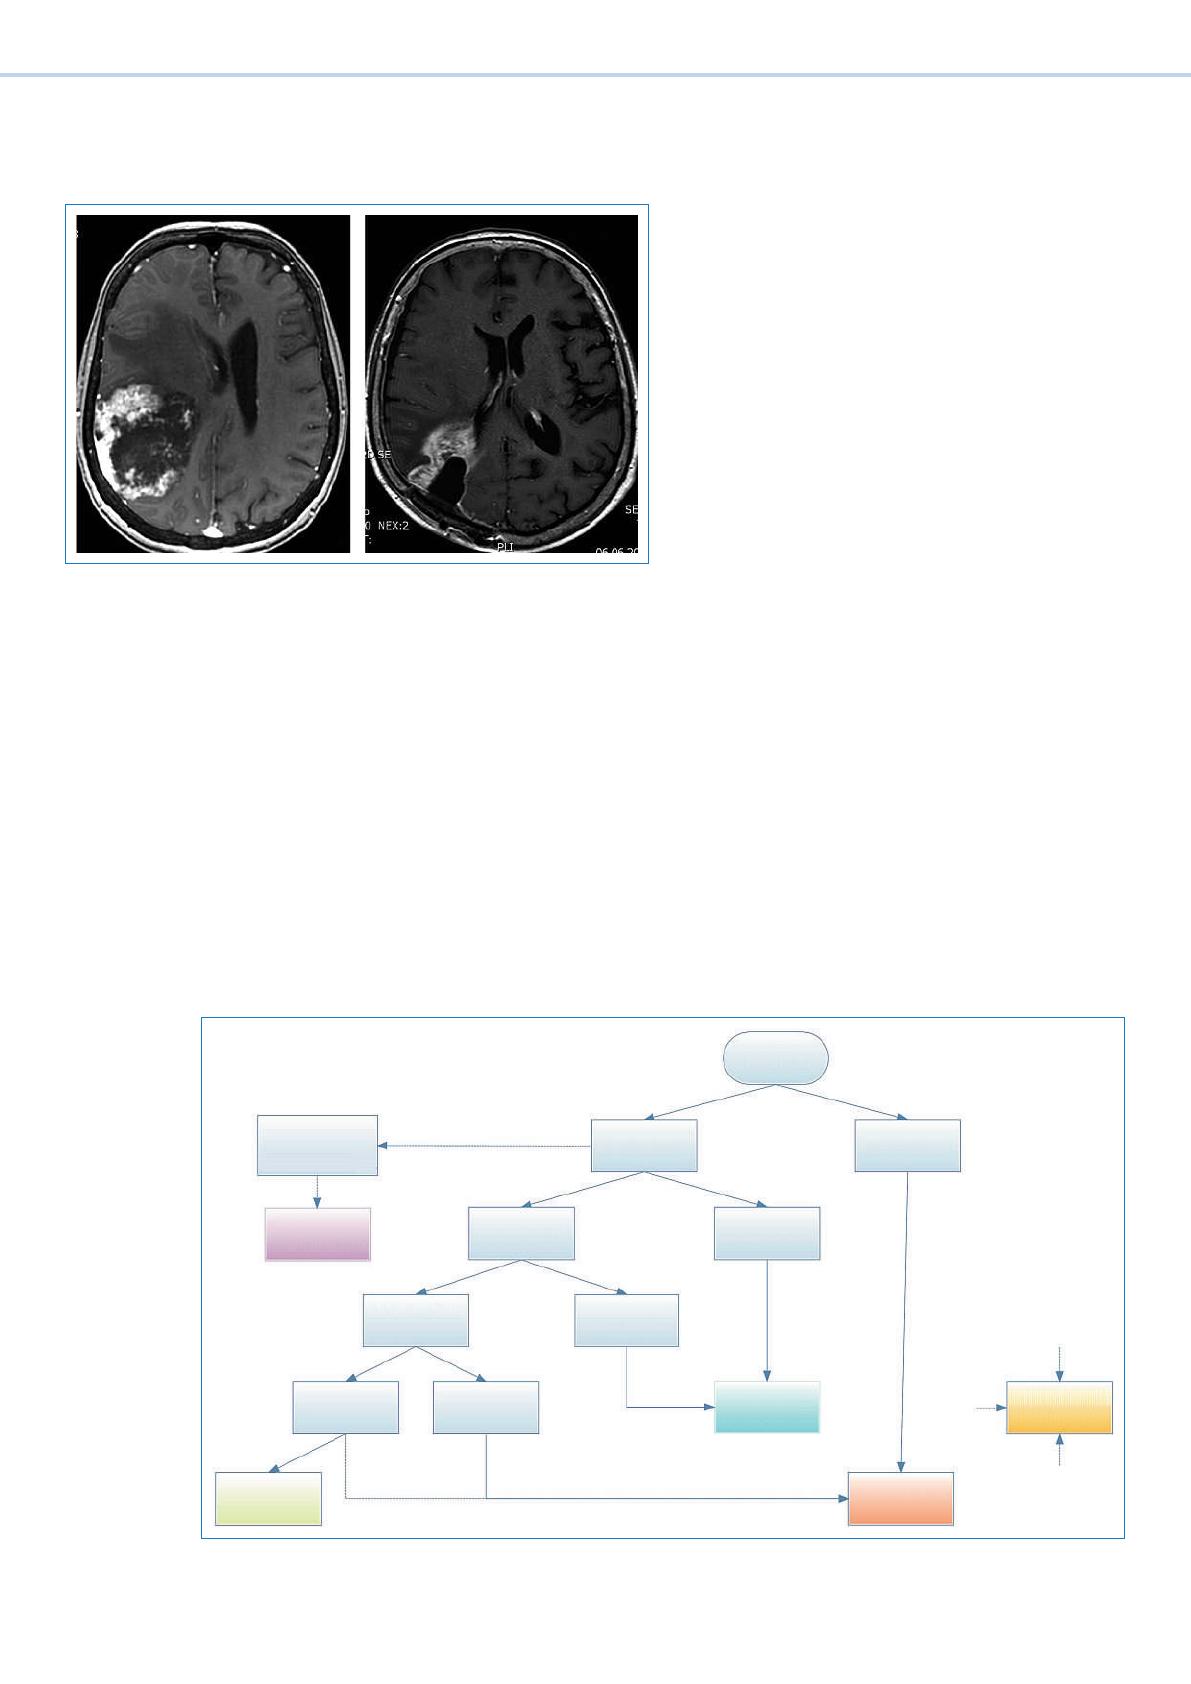

L’ évaluation du pronostic est nécessaire en cas de dé-

couverte de métastases cérébrales dans l’optique de la

planication du traitement. En cas de facteurs pronos-

tics favorables, un traitement local (chirurgie ou radio-

thérapie stéréotaxique) est indiqué. En cas de maladie

systémique bien contrôlée et d’un petit nombre de mé-

tastases (93), on peut reporter la radiothérapie du cer-

veau entier jusqu’à l’apparition d’une récidive au niveau

cérébral, sans compromettre la survie des patients et

avec une meilleure qualité de vie. Dans les entités tumo-

rales sensibles à la chimiothérapie et/ou en présence de

métastases extra-cérébrales, il peut être judicieux de

proposer un traitement systémique seul ou en combi-

naison avec une radiothérapie du cerveau entier.